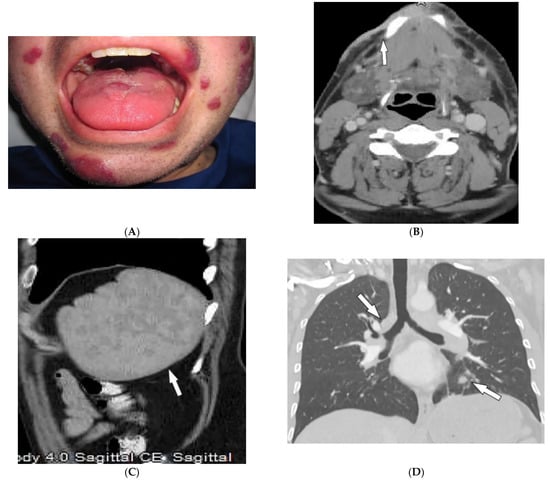

2.7. Behcet’s Disease

| Behcet’s disease | Oral and genital ulcers Ocular findings Vasculitis CNS lesions | Thickening of the aorta and SVC Bilateral pulmonary artery aneurysms Basal ganglia and brainstem lesions |

| Kaposi sarcoma | Erythematous or violaceous macules, plaques, nodules Pulmonary involvement Gastrointestinal involvement | Nodular enhancing masses Peribroncovascular nodules and halo sign |